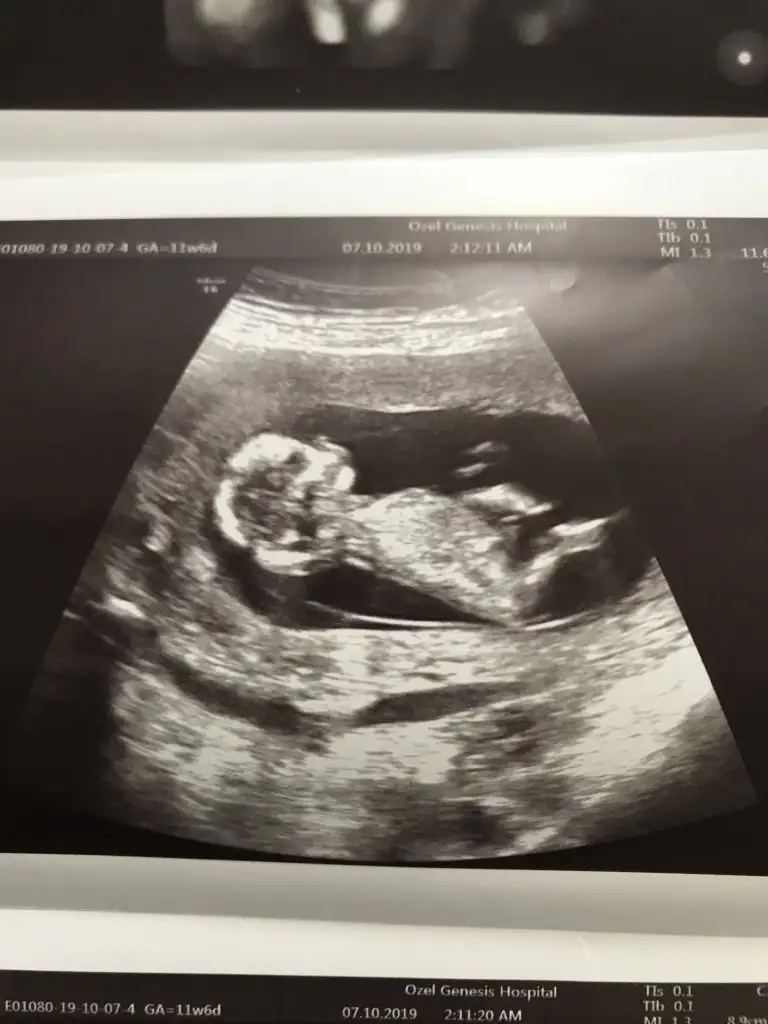

Ikra meyra Ikra meyra 12+3 ultrason görüntüsü cinsiyet tahminini alabilirmiyim canım☺️🤗

• 94857660-ABA5-471E-92AE-AB52510D2D61.webp

94857660-ABA5-471E-92AE-AB52510D2D61.webp

45,6 KB · Görüntüleme: 54